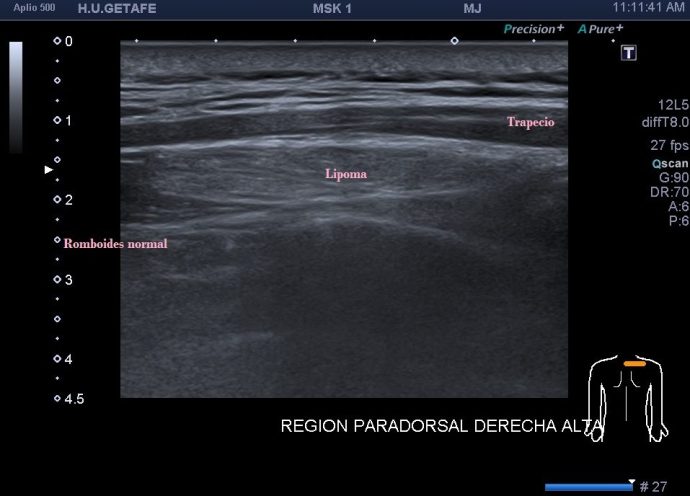

Como hoy quiero que este post sea muy visual y de poca lectura te voy a mostrar los diferentes lugares claves y básicos para que puedas estar atenta en las exploraciones para buscar líquido en estas localizaciones. Primera imagen de normalidad, segunda imagen de «no normalidad» y anatomía y ordenada según la clasificación que has visto un poco más arriba.